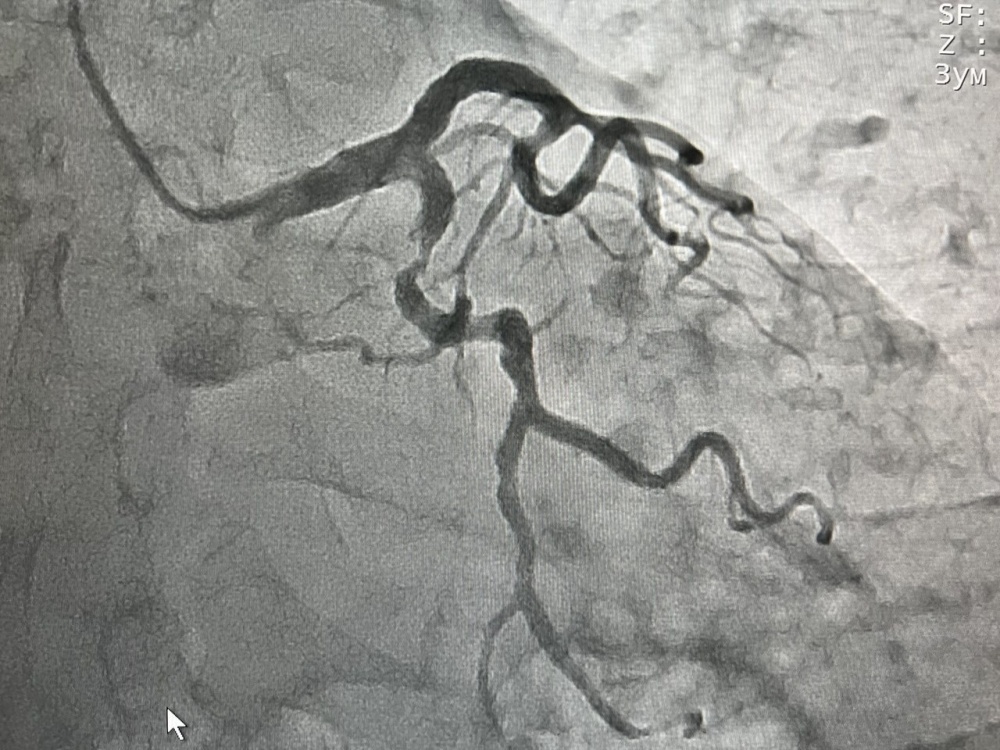

В отделение рентгенохирургии Южного регионального научного центра сердечно-сосудистой хирургии в Жалал-Абаде уже с марта привозят больных с различными сердечными патологиями, в том числе с острым коронарным синдромом из сел и райцентров Жалал-Абадской области. В начале апреля 28 пациентам проведена ангиография, благодаря этому методу контрастного рентгенологического исследования врачи на экране видят чёткое изображение сосудов сердца, их сужения и аномалии. Нескольким из этих больных рентгенохирурги установили стенты, чтобы предотвратить инфаркт миокарда, четверым - уже с острым инфарктом миокарда. Оказана необходимая помощь и пациентам при других формах коронарных синдромов.

На снимках представлено видео стеноза аортального клапана до лечения, в процессе баллонной дилатации и после имплантации и стентирования